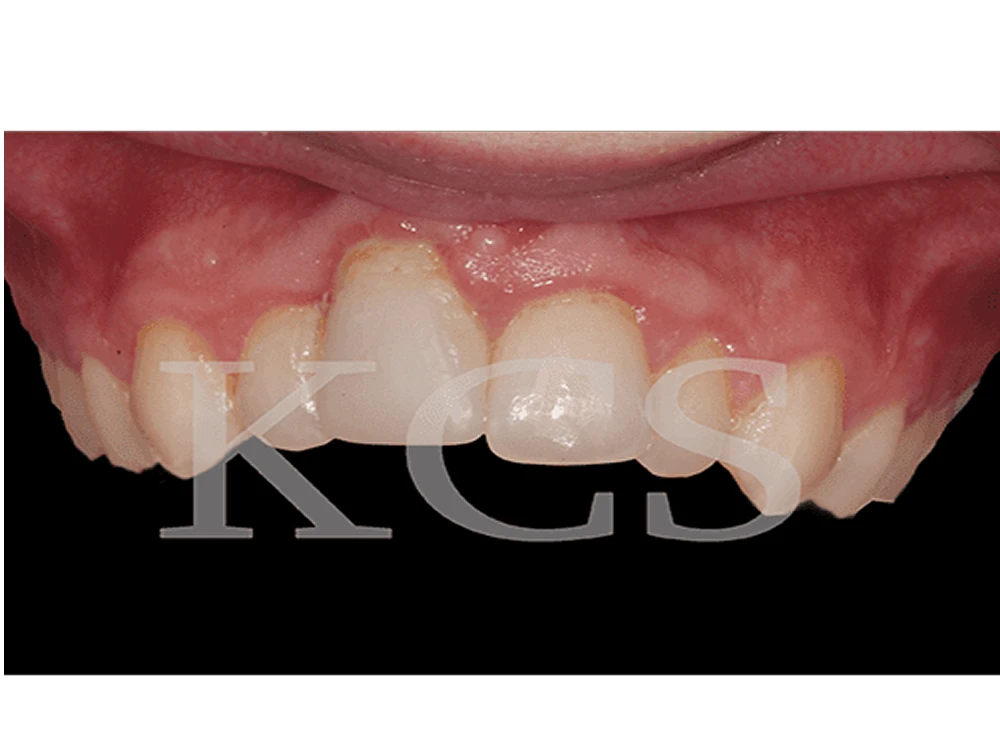

Patienten hade råkat ut för en olycka som drabbat höger framtand. Denna händelse resulterade i en långsamt permanent skada. I samarbete med den remitterande tandläkaren återställdes framtanden med hjälp av implantat.

Patientfall tandimplantat malmo tandimplantat Malmö

Röntgenbild visar den skadade tanden höger överkäke på patienten.

Tanden avlägsnades.